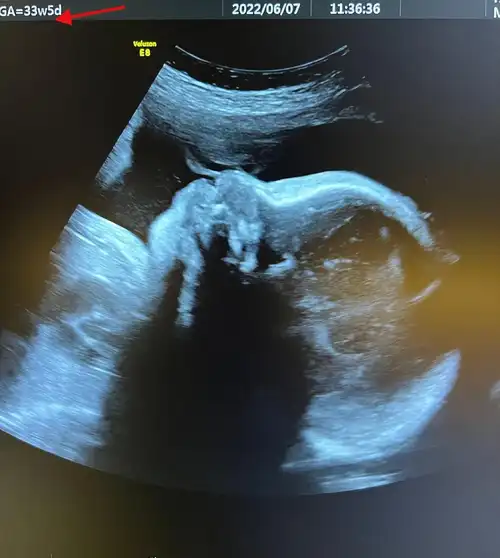

陈燃预产期将至,晒b超照曝二胎是男孩,提前公布宝宝性别惹争议_儿子